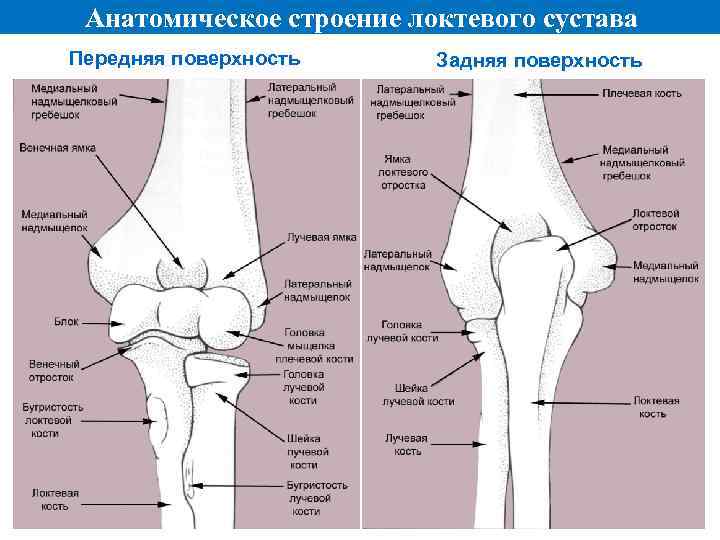

Анатомическое строение локтевого сустава Передняя поверхность Задняя поверхность

Анатомическое строение локтевого сустава Передняя поверхность Задняя поверхность

ЛОКТЕВОЙ СУСТАВ (articulatio cubiti) наиболее конгруэнтный сустав человеческого тела, что в значительной мере обусловлено конгруэнтностью плече-локтевого сустава, а именно точному соответствию суставных поверхностей блока и суставных поверхностей проксимального конца локтевой кости В локтевом суставе сочленяются три кости: • дистальный конец плечевой кости • проксимальные концы локтевой и л у ч е в о й к о с т е й Сочленяющиеся кости образуют три сустава, заключенные в одну сумку: • плечелоктевой • плечелучевой • проксимальный лучелоктевой

ЛОКТЕВОЙ СУСТАВ (articulatio cubiti) наиболее конгруэнтный сустав человеческого тела, что в значительной мере обусловлено конгруэнтностью плече-локтевого сустава, а именно точному соответствию суставных поверхностей блока и суставных поверхностей проксимального конца локтевой кости В локтевом суставе сочленяются три кости: • дистальный конец плечевой кости • проксимальные концы локтевой и л у ч е в о й к о с т е й Сочленяющиеся кости образуют три сустава, заключенные в одну сумку: • плечелоктевой • плечелучевой • проксимальный лучелоктевой